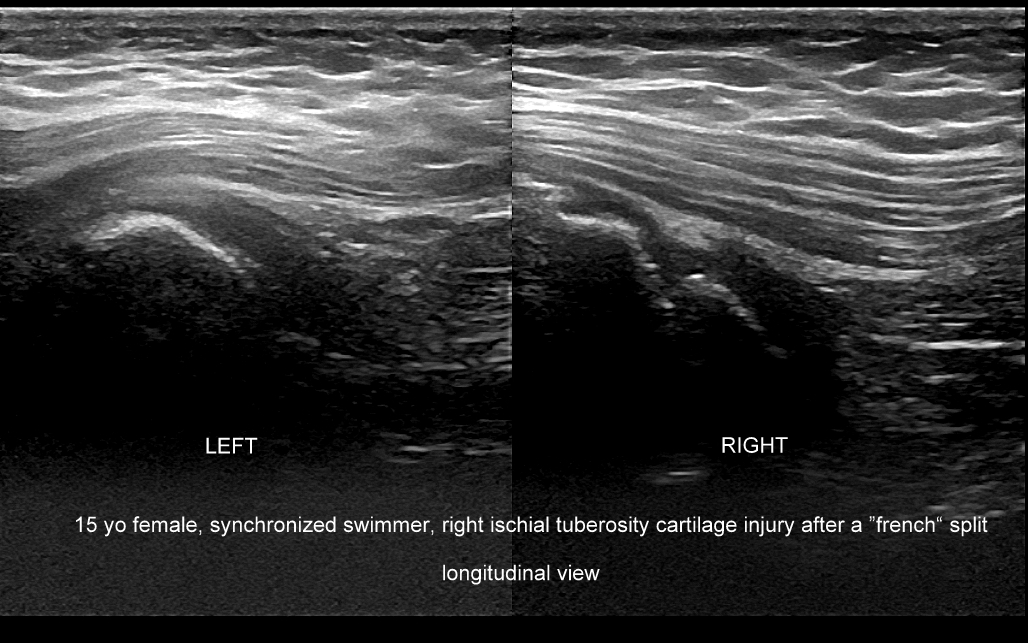

Badanie USG w obrębie uda najczęściej wykorzystywane jest przy diagnostyce urazów sportowych, wśród których dominują naderwania mięśni. Naderwania u dorosłych lokalizują się zwykle w okolicy przyczepu bliższego mięśnia czworogłowego uda, przyczepów bliższych i dalszych tylnej grupy mięśniowej (mięśnie półbłoniasty, półścięgnisty, dwugłowy uda) określanej zbiorczo z języka angielskiego jako hamstringi, a także w obrębie mięśni przywodzicieli. W mięśniach uda nierzadko u młodych dorosłych pojawiają się nowotwory mięsaki. U dorastających dzieci naderwania w zakresie jednostek ruchowych występują na przyczepach ścięgnisto-chrzęstnych lub chrzęstno-kostnych.